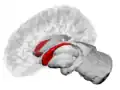

The caudate nuclei are near the center of the brain, sitting astride the thalamus. There is a caudate nucleus in each hemisphere of the brain. Each nucleus is C-shaped, with a wider "head" (caput in Latin) at the front, tapering to a "body" (corpus) and a "tail" (cauda). Sometimes a part of the caudate nucleus is called the "knee" (genu).[6] The caudate head receives its blood supply from the lenticulostriate artery; the tail of the caudate receives its blood supply from the anterior choroidal artery.[7]

The head and body of the caudate nucleus form part of the floor of the anterior horn of the lateral ventricle. The body travels briefly towards the back of the head; the tail then curves back toward the anterior, forming the roof of the inferior horn of the lateral ventricle. This means that a coronal section (on a plane parallel to the face) that cuts through the tail will also cross the body and head of the caudate nucleus.

Caudate nucleus highlighted in green on sagittal T1 MRI images -